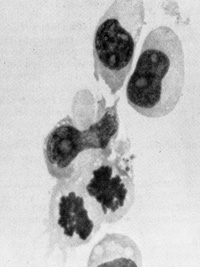

Fig. 4. Morphology of „immortalized cell line induced from normal human blood after infection by Ganot IVH and EBV positive ( Magnification 1000 x )

Fig,5. B-Cell lymphoma of nude mouse induced by injection of mouse with cells induced to grow by GaLVH Cells are human as determined by karyotype analysis. (From P Markham, F Ruscetti. Z. Salahuddin, R Gallagher. and R. Gallo. in press)